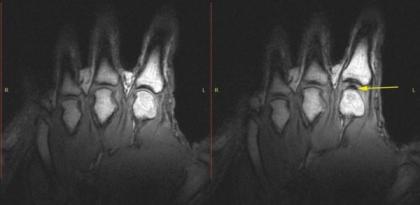

为了控制脆响并用MRI捕捉到这个瞬间,研究员们在Fryer的手指上连接了电子管,然后慢慢拉直到手指发出声响。

被连接的手指只有一根(尽管他提供了十根手指),MRI并没有记录到什么实际的声音,所以这次研究实际上还是没有确凿证据能终结这场争论。但就检测了的单个手指的脆响而言,在研究人员听到声音时手指关节中确实出现了一个洞。而且,Kawchuk及其同事并没有发现空洞有任何破裂的痕迹,至少在指节发出声响之后不久的时间里,所以他们不认为是所谓起泡破了发出的声音。